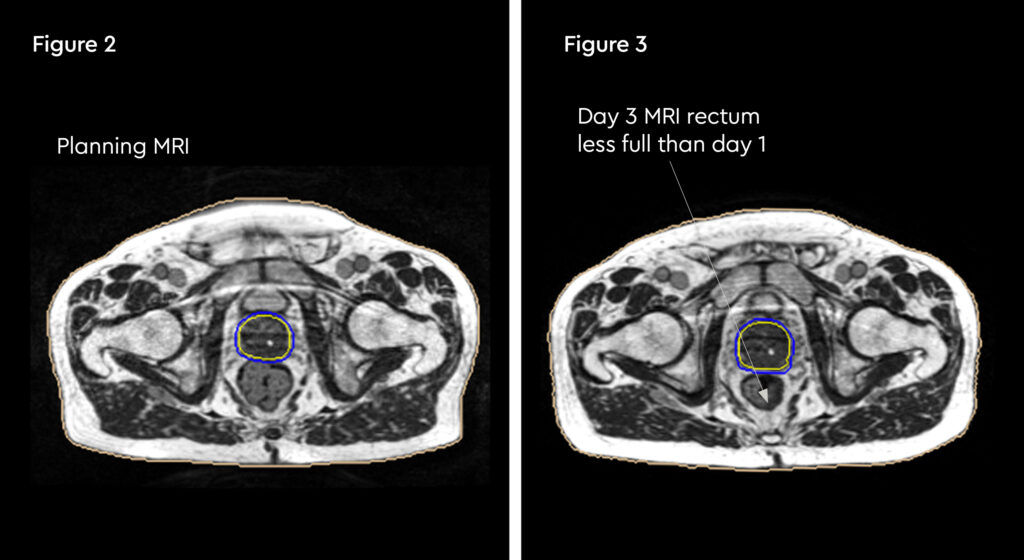

At each session, daily adaptation was performed to account for changes in the position of the prostate and for variable bladder and bowel filling. Figure 1 and figure 2 illustrate the typical differences seen between the original planning MRIdian scan and that seen on the day of treatment due to day-to-day organ movement. Figure 3 and figure 4 illustrate how these movements were accommodated with the on-table plan adaptation.

Fig 3: Changes in internal anatomy demonstrated by a smaller rectum on day 3 compared to the planning scan

Fig 4: Changes in internal anatomy demonstrated by a different rectum size on day 4